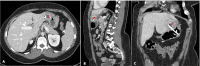

Endoscopic sleeve gastroplasty is a minimally invasive procedure for the treatment of obesity. The procedure is generally safe and well-tolerated, but major adverse events occur in up to 3% of patients. Perigastric abscess is a potential complication caused by postprocedural gastric leak. To the best of our knowledge, no cases of hepatic abscess (HA) following endoscopic sleeve gastroplasty have been reported, while HA is a well-known complication of laparoscopic sleeve gastrectomy. We report the case of a patient who developed a liver abscess 2 weeks after endoscopic sleeve gastroplasty. The patient improved with administration of intravenous antibiotics and endoscopic drainage.